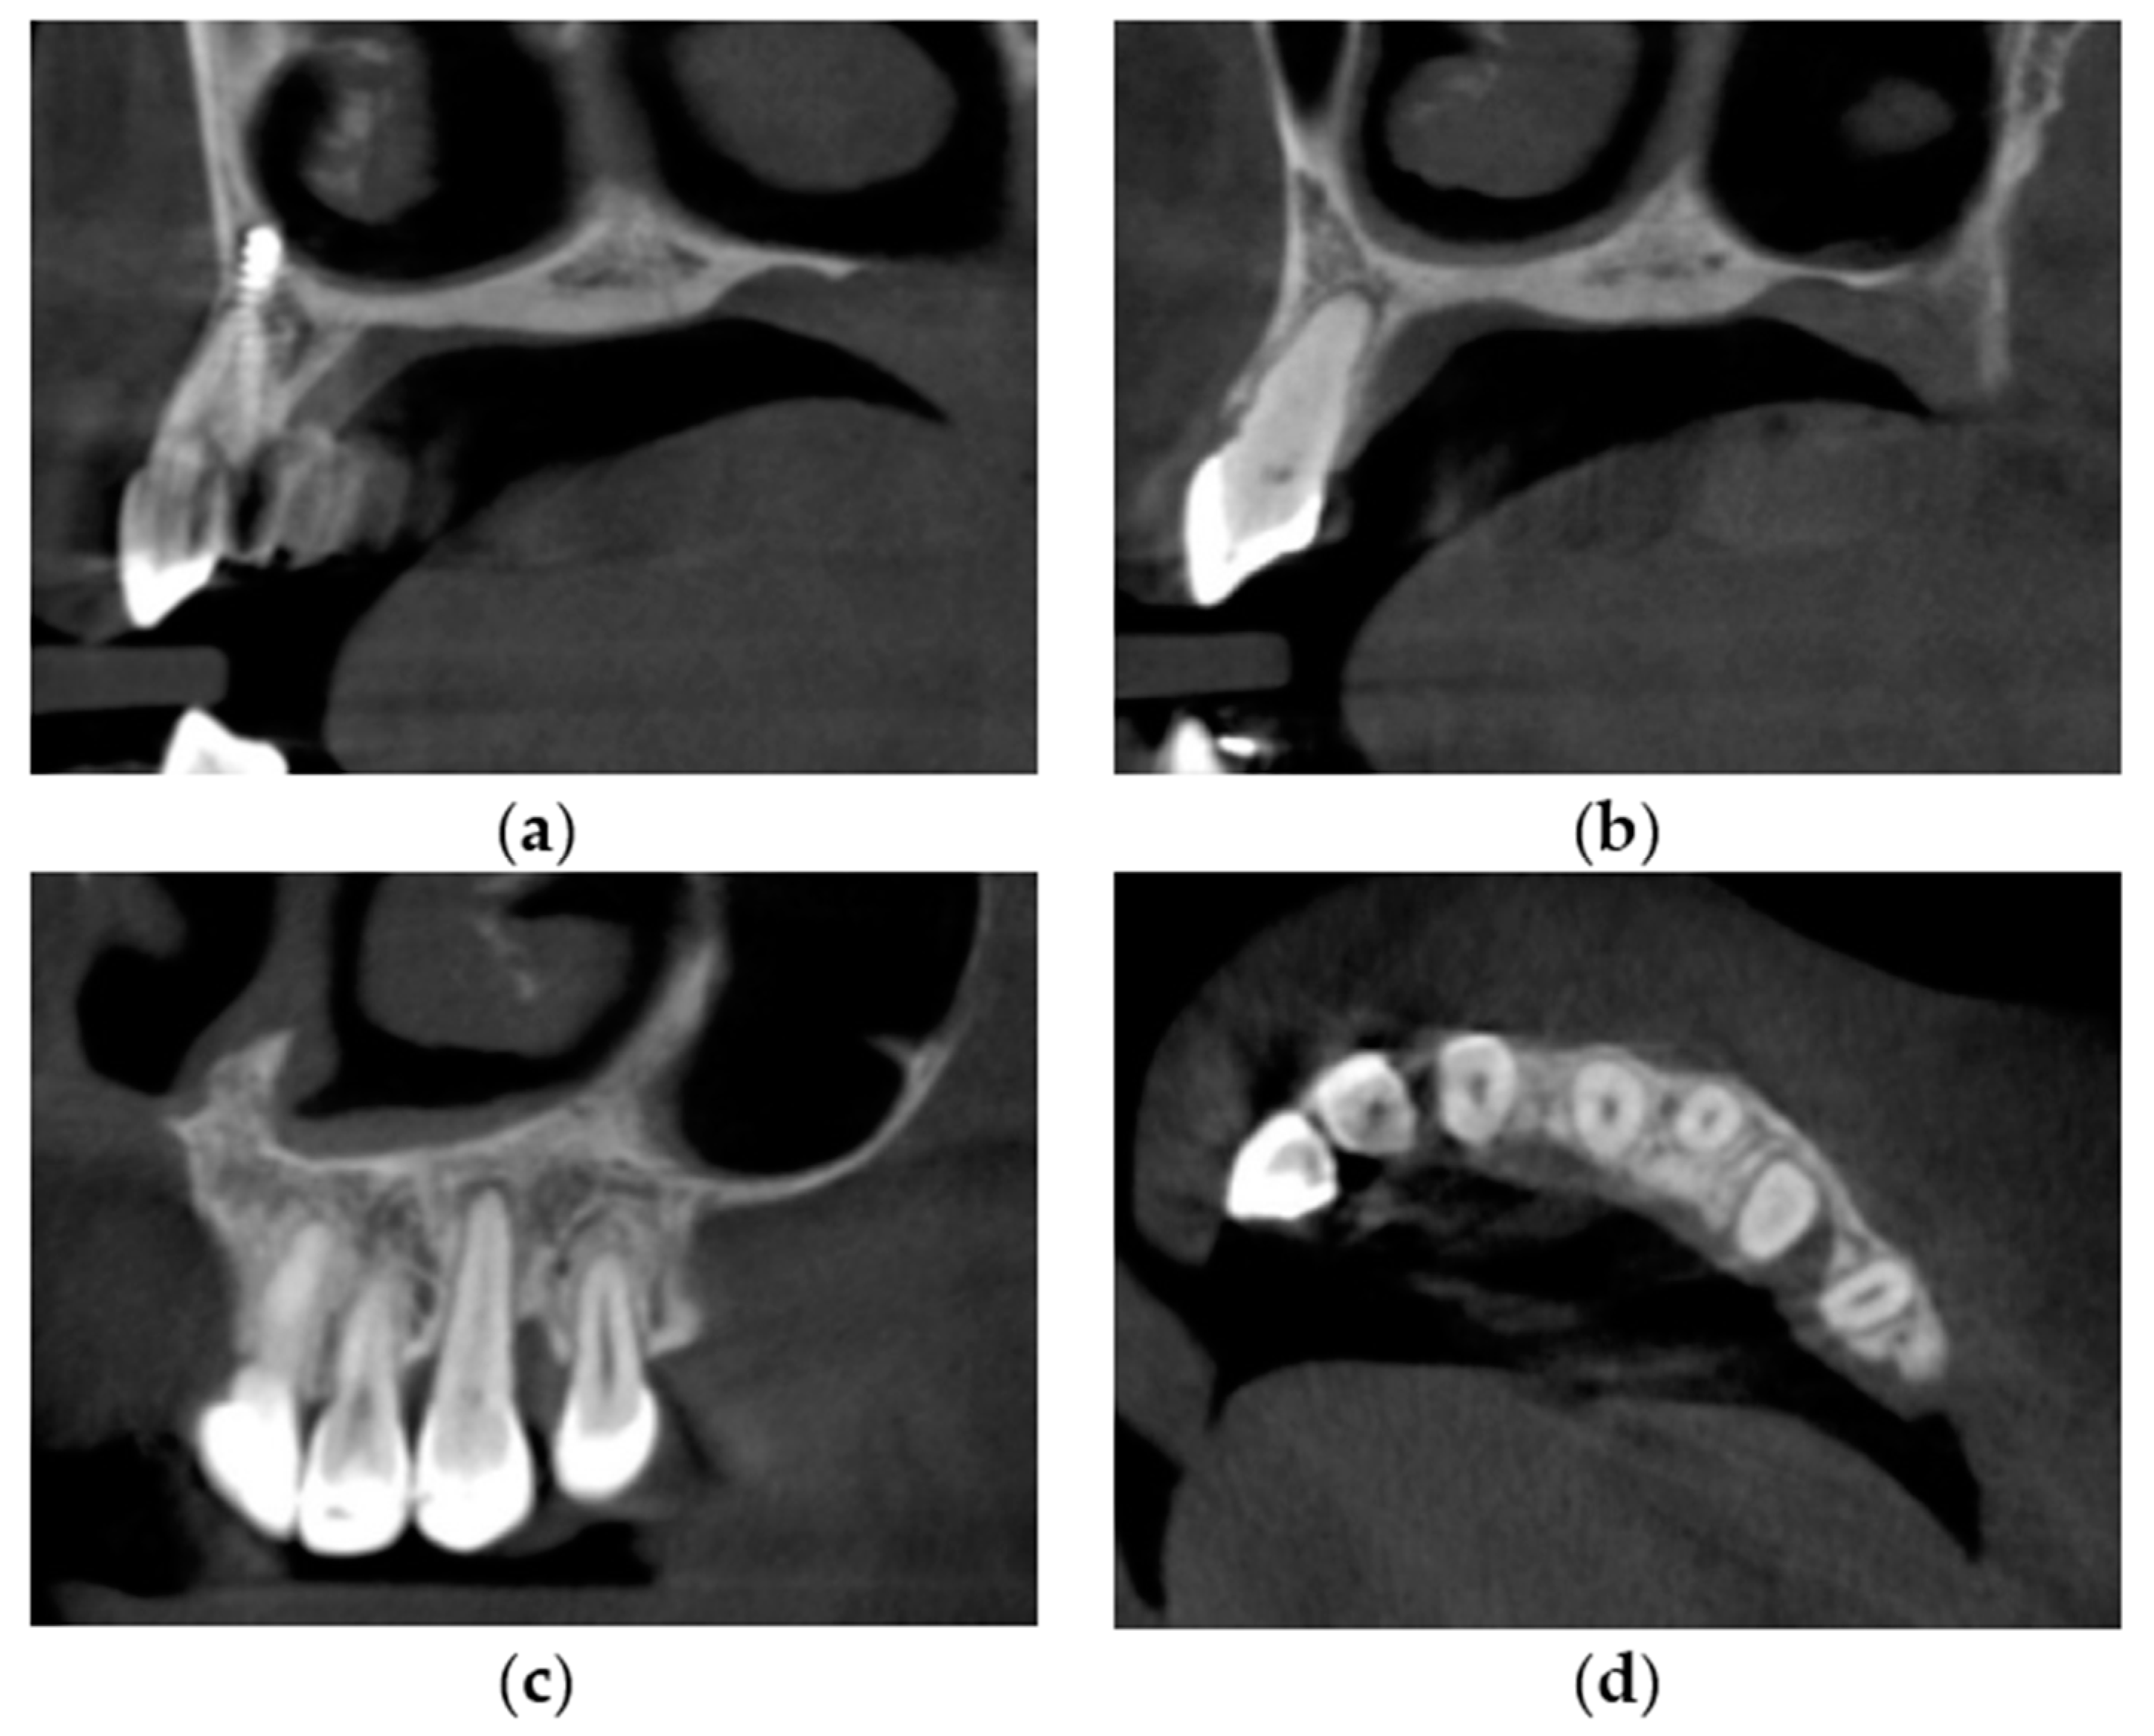

| Tooth Number | 13 | 12 | 11 | 21 | 22 | 23 | 24 |

|---|---|---|---|---|---|---|---|

| Root length before treatment (mm) | 11.5 + 2.1 * | 12.9 | 11.1 | 10.8 | 12.8 | 14.6 | 9.4 |

| Root length after treatment (mm) | 11.0 | 12.3 | 10.5 | 9.5 | 10.9 | 12.4 | 8.5 |